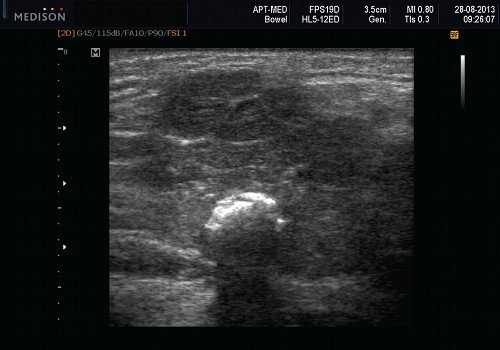

Рис. 5. Камень протока поднижнечелюстной слюнной железы.

Рис. 6. Камень в паренхиме поднижнечелюстной слюнной железы.

Рис. 7. Камень в протоке поднижнечелюстной слюнной железы.